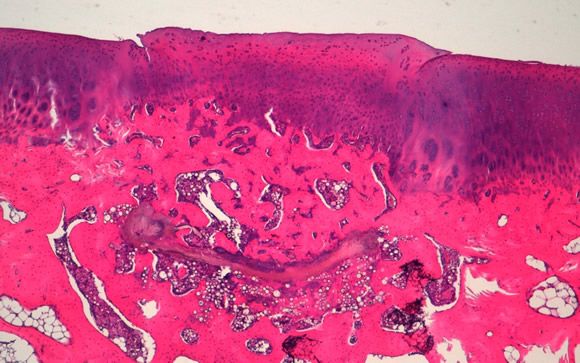

El resultado de esta combinación es la producción de un material que se coloca en el lugar dañado. Según estudios preliminares en conejos, se ha demostrado que, al cabo de tres meses, el organismo ha sido capaz de desplazar el material colocado anteriormente y lo ha sustituido por tejido con aspecto histológico del tejido natural y con una superficie articular totalmente funcional.REVISADO POR EL MIT